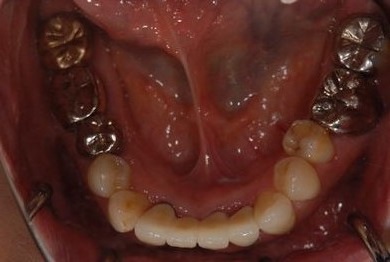

| 治療方針 | 保存不能な歯を抜歯し、セラミック治療にて、機能的・審美的回復を行う。 | ||||||||||||||||||||||||||||||||

| 治療内容 | ジルコニアオールセラミッククラウン4本(オールセラミック用土台3本) | ||||||||||||||||||||||||||||||||

| 総治療費 | 799,050円 | ||||||||||||||||||||||||||||||||

| 治療期間 | 5ヶ月 |